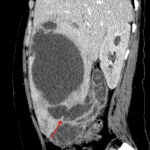

Indication: Right-sided abdominal pain

Findings

- Lower chest

- Mild dependent right basilar atelectasis

- Abdomen/Pelvis

- Gallbladder wall thickening and enhancement with mural discontinuity along the ventral margin near the fundus with a contiguous large multiloculated, peripherally-enhancing collection measuring 13 x 8 x 16 cm in the right hepatic lobe involving segments 5 and 6

- Multiple rounded peripherally hyperdense structures in the gallbladder and in the dependent aspect of the hepatic collection consistent with gallstones

- 1.7 cm hypodense lesion in segment 2 of the liver with possible discontinuous peripheral enhancement

- Mild intrahepatic biliary duct dilation

- Small volume free fluid layering in the anatomic pelvis

Diagnosis

- Perforated acute cholecystitis with hepatic abscess

Findings consistent with perforated acute cholecystitis with a large contiguous right hepatic abscess. Recommend surgical evaluation.

Mild intrahepatic biliary duct dilation likely resulting from mass effect from the large hepatic abscess on the hepatic hilum.

Hypodense structure in the left hepatic lobe may represent a hemangioma or less likely a satellite abscess. This could be further evaluated with ultrasound.